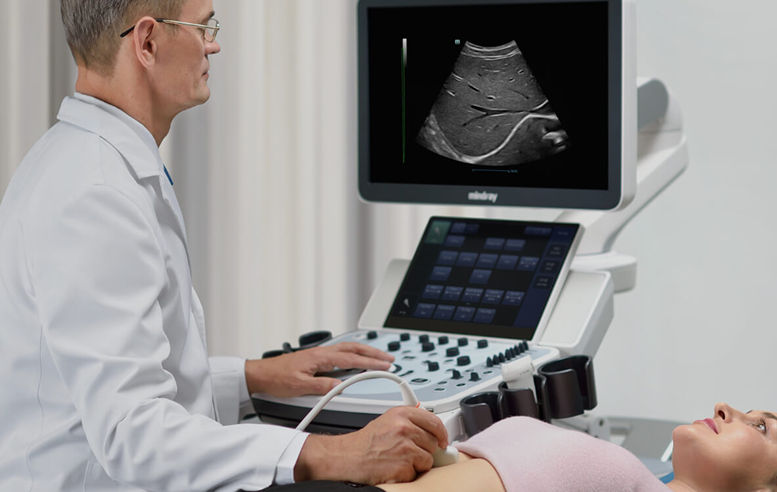

Mindray stellt mit seinen innovativen Sonographiesystemen unter Beweis, worauf es in der haus?rztlichen Diagnostik ankommt. Der Einsatz anerkannter Bildgebungstechnologien wie iClear und iBeam macht das DC-30 mit Full HD sehr leistungsstark und hochwertig. Eine clevere Kombination von Ultraschallsonden mit spezialisierten Schallk?pfen unterstĂŒtzt erstklassige? Ergebnisse in einem breiten Anwendungsspektrum. Mit Hilfe der Breitband-Schallk?pfe l?sst sich eine Vielzahl an Patiententypen erfolgreich untersuchen

Der Einsatz anerkannter Bildgebungstechnologien macht das DC-30 mit Full HD sehr leistungsstark und hochwertig. Sie sind erfolgreich aus etablierten Ultraschallsystemen migriert worden. Eine clevere Kombination von Ultraschallsonden mit spezialisierten Schallk?pfen unterstĂŒtzt erstklassige Ergebnisse in einem breiten Anwendungsspektrum. Mit Hilfe der Breitband-Schallk?pfe l?sst sich eine Vielzahl an Patiententypen erfolgreich untersuchen. Diese bew?hrten Ultraschalltechnologien sorgen fĂŒr eine h?here Diagnosequalit?t:

Die Optimierung von besonderen und allt?glichen Arbeitsabl?ufen gelingt dem DC-30 Full HD auf intelligente Weise. Das h?henverstell- und schwenkbare Bedienfeld wird durch den um 215 Grad drehbaren HD-Monitor erg?nzt. Es erm?glicht auch unter schwierigen Rahmenbedingungen ein komfortables Arbeiten.